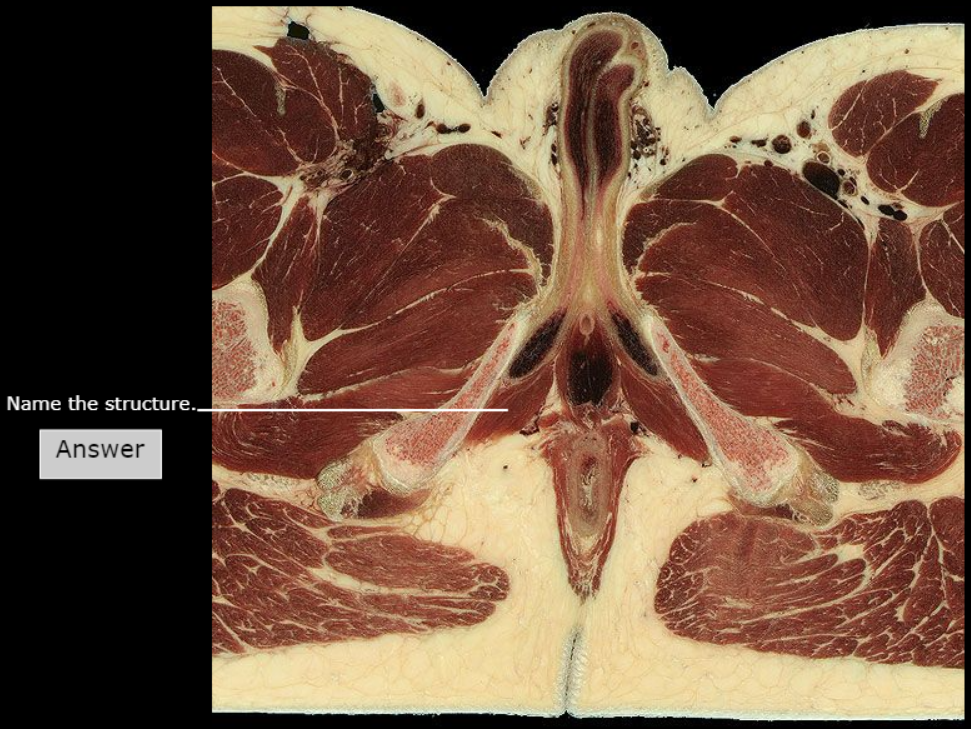

Levator ani